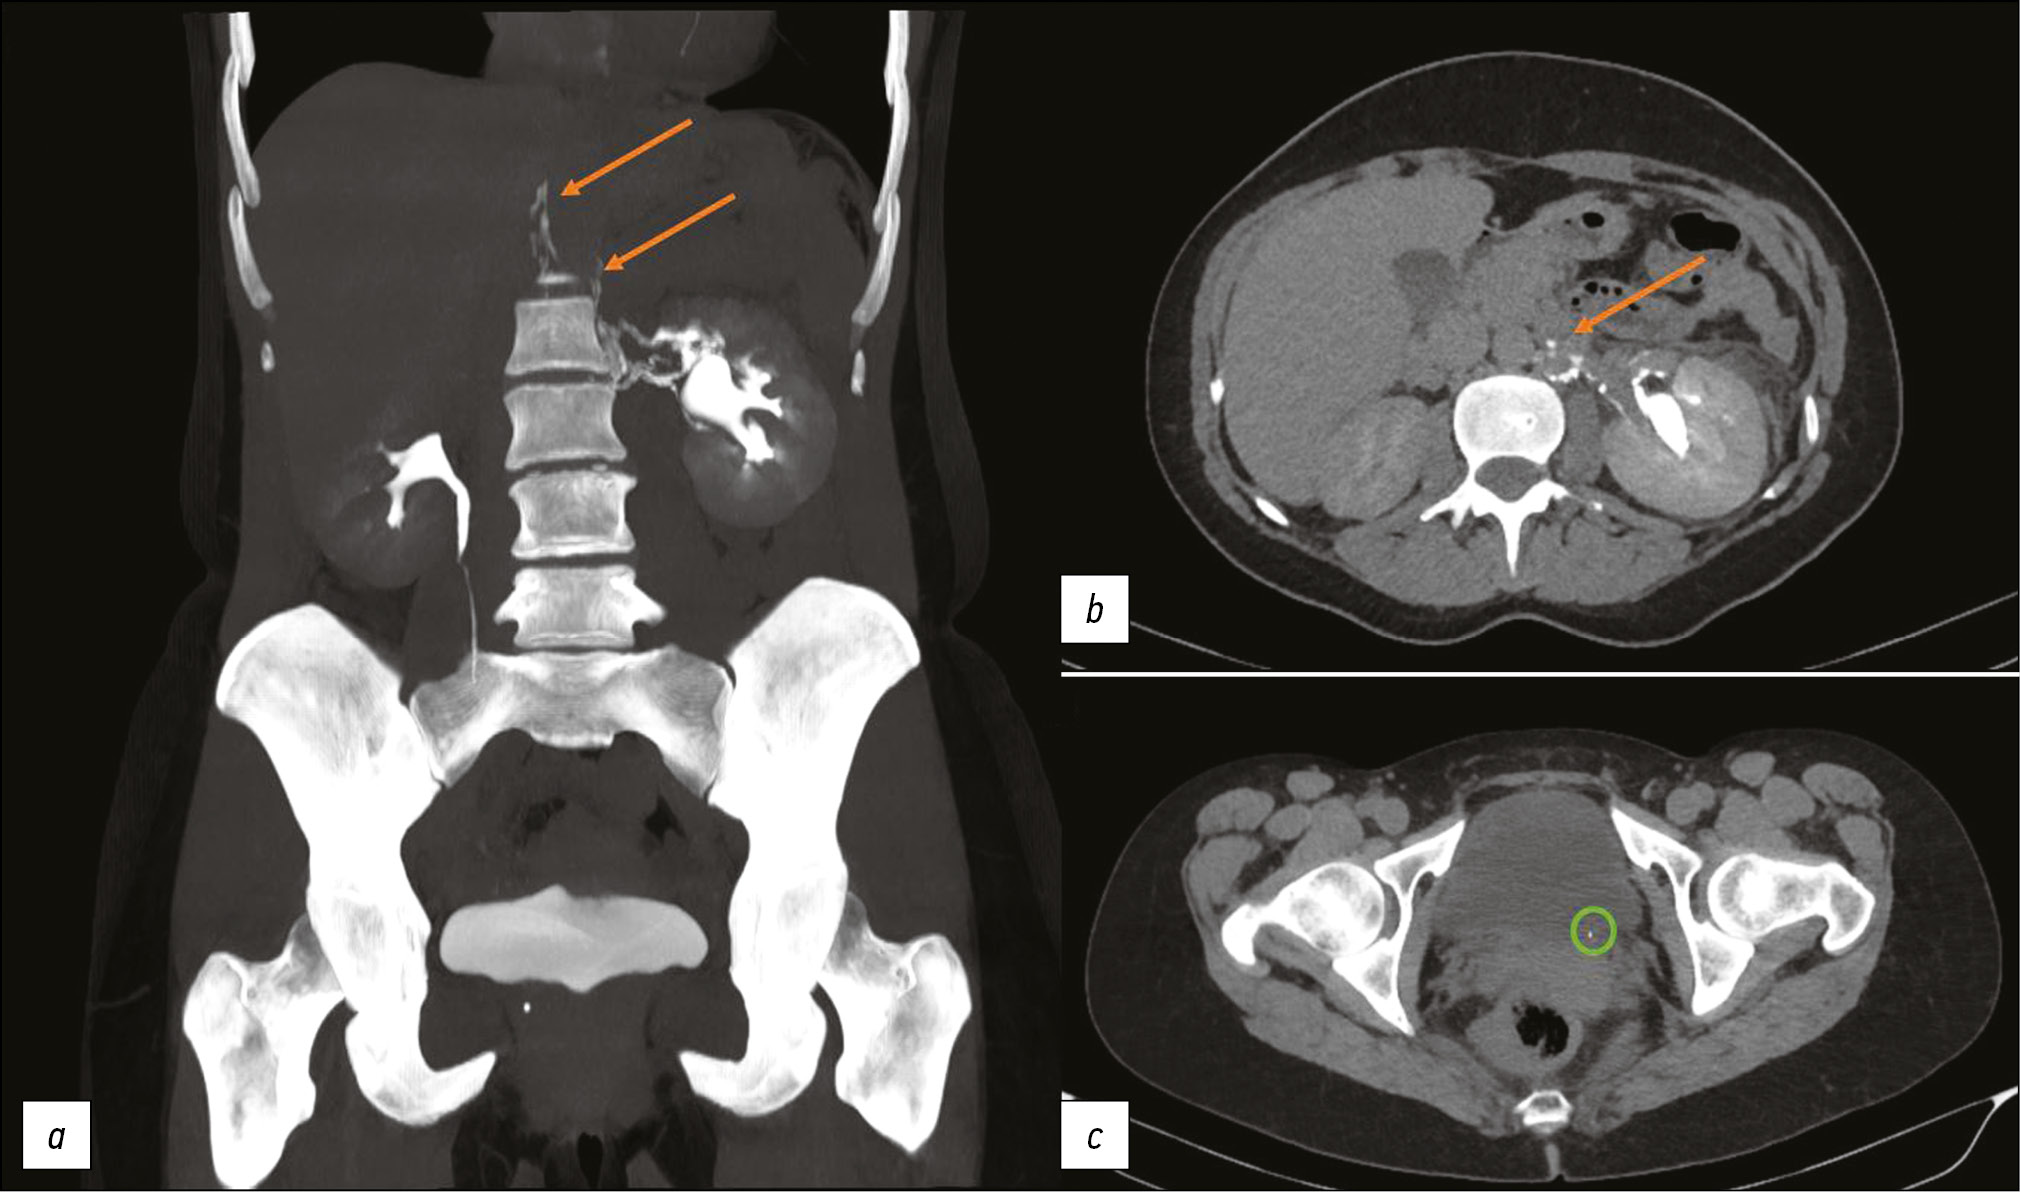

At 15 min, the CT revealed a small peripelvic contrast extravasation (urinoma) (during the delayed phase). In addition, the retrograde contrast enhancement of lymphatic vessels was observed along the left renal vein during the excretory phase. These signs are typical for ULF. The examination showed the calculus at the left ureteric orifice, left ureteropyelocalicoectasia, left peripelvic urinoma, and right renal calculus (Figure 1).

Fig. 1. Computed tomography of the abdomen with intravenous contrast enhancement. The excretory phase: (a, b) Orange arrows show the contrast spreading along lymphatic vessels; (c) A green circle highlights a calculus at the left ureteric orifice.